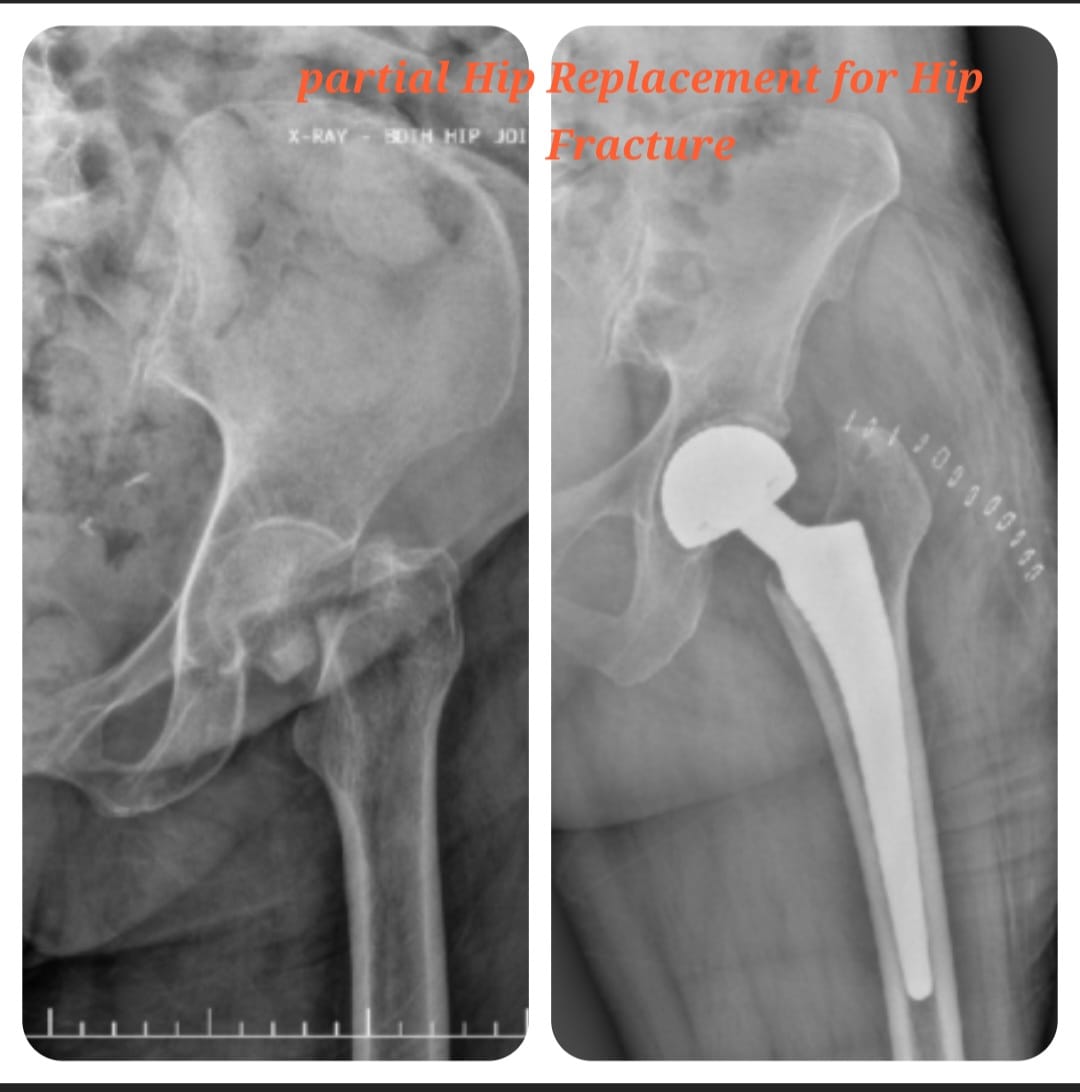

Hemi hip replacement, also known as hemiarthroplasty, is a surgical procedure commonly performed to treat fractures of the hip, especially in elderly patients. The procedure involves replacing only the femoral head (ball) of the hip joint while preserving the natural acetabulum (socket), allowing pain relief and early restoration of mobility.

This procedure is particularly beneficial for patients with poor bone quality or limited pre-injury mobility. Careful patient selection, accurate implant positioning, and modern surgical techniques help ensure stable fixation, faster recovery, and reduced postoperative complications.